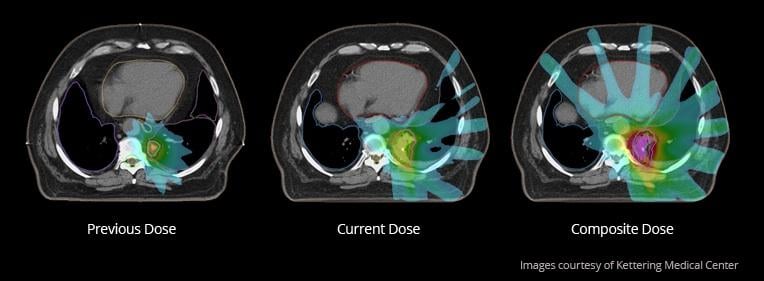

March 24, 2014 — Medical physicists met in Denver, Colo., March 15-18 for the American Association of Physicists in Medicine (AAPM) Spring Clinical Meeting, hosted at the Denver Marriott Tech Center. The meeting focused on helping medical physicists with the integration of emerging technologies into the clinical environment. Mirada Medical demonstrated its comprehensive suite of advanced deformable image registration (DIR) software tools to meeting attendees. The company utilizes its scientifically advanced DIR algorithms to provide practical tools to support treatment planning.

Mirada’s scientists have made their algorithms application and modality specific — carefully tuning internal parameters, such as deformable field smoothness, degree of freedom and similarity function sensitivity. This provides a strong basis for multi-modality contouring, auto contouring, dose deformation and composite dose, and it provides support for adaptive therapy and re-treatment decisions.